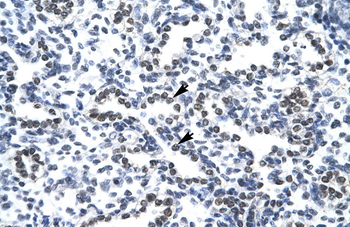

ICC, IF, IHC-Fr, IHC-P, WB | |

Mouse, Rat | |

Human, Mouse, Rat | |

Rabbit | |

Recombinant | |

Unconjugated |